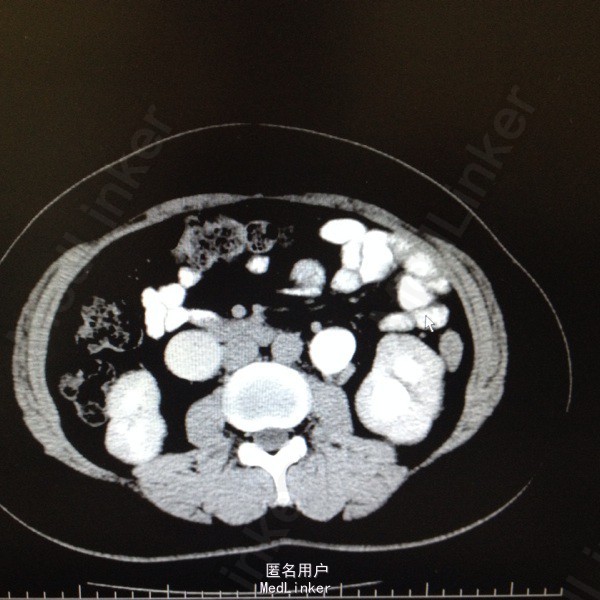

47岁女患。 病史:患者6年前因宫颈癌行全子宫及双侧附件切除。盆腔淋巴结清扫。腹主动脉旁淋巴结活检术。后又行局部放疗。因双肾积水来我科。患者自述平时轻微排尿困难,尿线细。

双肾区无叩击痛,双输尿管走形区无压痛。耻骨上区隆起,叩诊浊音。排尿后留置尿管引流尿液400ml。 辅助检查:肌酐99。 ct:双肾及输尿管积水。 留置尿管后一周泌尿系彩超:双肾积水明显减轻。具体见图片。

诊断:双肾及双输尿管积水 神经源性膀胱 给予患者留置尿管后1周行泌尿系彩超检查肾积水减轻。

宫颈癌根治及放疗后双肾积水情况较多见,常因输尿管壁内段狭窄或神经源性膀胱引起。此患者留置尿管后肾积水明显减轻。建议患者继续留置尿管或间断家庭导尿治疗。